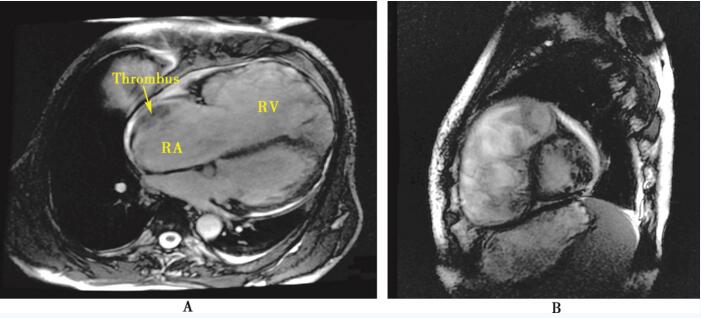

图10-3 心脏磁共振成像

A:横断面显示右心房、右心室显著扩大,右心房可见附壁血栓形成; B:矢状面显示右心增大,其内可见血流淤滞的涡流信号

心脏磁共振成像:心脏呈普大型,右心房、室明显增大,收缩、舒张功能明显减低;右心房内近前壁处可见一条片状低信号影,边界尚清,约2.5cm×1.4cm,周边可见血流信号;心脏显影右心房、心室内可见涡流,收缩期三尖瓣口可见大量反流信号,右心室心肌明显增厚并分层,外层心肌明显变薄呈线状,内层心肌明显增厚,其内可见多发粗大的肌小梁呈网格状排列。结论:右心明显增大伴房室壁变薄,符合心肌致密化不全;右心房近前壁处低信号影,考虑血栓不除外;重度三尖瓣反流(图10-3)。